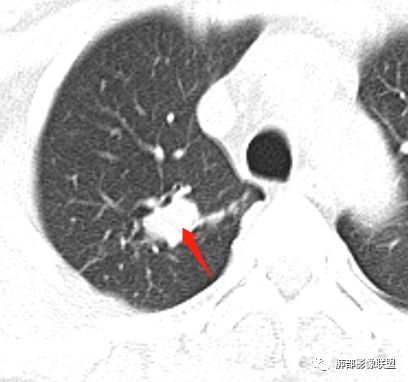

患者中年男性,主诉:咳嗽  胸痛。  胸CT:右肺上叶尖段占位,病灶位于支气管外,病灶周围部分区域可见毛玻璃影,病灶边缘不规则,部分区域可见平直,胸膜牵拉(无胸膜凹陷),柔软长毛刺,分叶,纵隔窗病灶没可见低密度区,左肺尖可见一点状病灶,病灶整体考虑良性疾病:感染性病变(结核?),感染后机化?。恶性病变待除外。

晨读:患者中年男性,反复咳嗽1月余,伴左胸部疼痛1周就诊。胸部CT:右肺上叶尖后段不规则结节,见长毛刺、胸膜牵拉、条索影,周围见卫星灶。未见明显淋巴结肿大,符合结核病变。鉴别其他。但其病灶位于右肺,主诉左胸痛,是误写,还是?

一米阳光:    晨读,右上肺结节影,形态不规则,边缘平直,部分凹陷,长软毛刺,胸膜牵拉,周围卫星灶。考虑结核。鉴别腺癌,部分边缘彭隆

灵魂清零: 右上肺结节影既有良性征象也有恶性征象,良性:边界平直,形态扁平,左肺尖有病灶;恶性:周围边界清楚的磨玻璃影,内部密度不均匀,局部边界有膨隆!考虑腺癌,肉芽肿病变待排!进一步增强扫描!再穿刺活检检查!

小飞:  晨读:右肺上叶不规则结节灶,沿支气管走形分布,边缘平直,U型凹陷,脊柱侧有少许磨玻璃影,左肺尖少许斑点灶,综合考虑结核。

纵隔窗提示内侧部分密度不够实

边缘平直、凹陷为主,部分膨隆

内部小点状影提示可能支气管腔内粘液栓

左肺尖及右肺病灶附近见小斑点,边界尚清

南边:2、不踏实的地方:GGO是不是容积效应所致?如果薄层,边界清楚GGO,就考虑继发瘢痕癌

因此我们需要的是:薄层、重建,看GGO边缘、看整体形态

结果:结核合并真菌(曲霉菌)感染